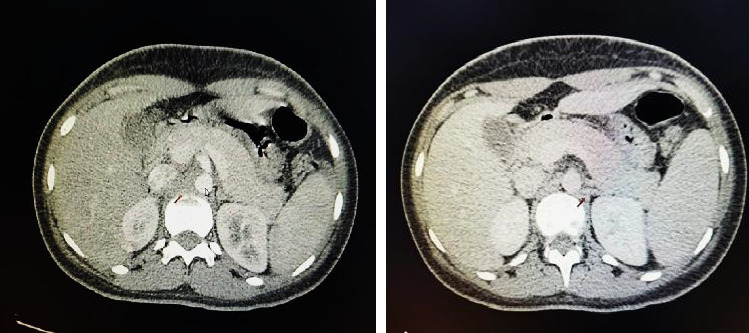

The increase in the incidence of dengue cases in the region has led to the identification of multiple complications associated with the disease. The present study presents the case of an adolescent girl with severe dengue in a hyperinflammatory state, who presented mild acute pancreatitis. This complication, although infrequent, can be harmful. In the clinical case presented, the patient presented severe dengue, according to the clinical diagnosis. In addition, polyserositis was observed, with positive NS1, IgG, and IgM, elevated transaminases above 1000 U/L and elevated levels of inflammatory markers such as ferritin, LDH, procalcitonin, and decreased fibrinogen. The diagnosis of acute pancreatitis was established based on two main criteria: elevated serum lipase/amylase and imaging studies. The patient did not experience significant abdominal pain; however, she manifested intense and persistent nausea for a period of 3 days. Despite presenting no other risk factors for acute pancreatitis, the patient was suffering from an infectious process. Treatment consisted of a complete 24-h fast and adequate hydration, which resulted in a progressive improvement in the patient's condition.